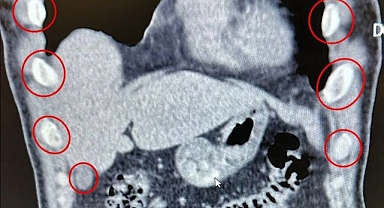

Midelerini kurye olarak kullandılar! Kapsül kapsül bakın ne taşıdılar...

Böbreğinden geyik boynuzu çıktı